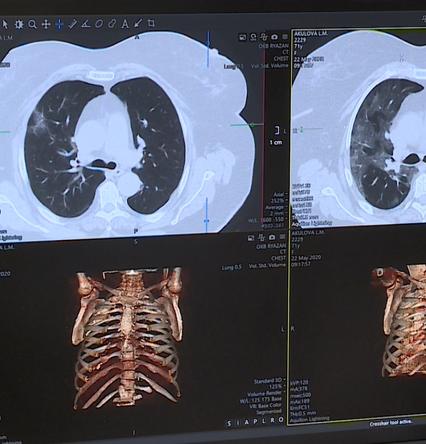

Врачи ОКБ первыми в России начали тестировать лекарство от COVID-19

Пятеро пациентов ОКБ первыми в России тестируют лекарство от коронавируса. Врачи уже назвали его «таблеткой надежды».